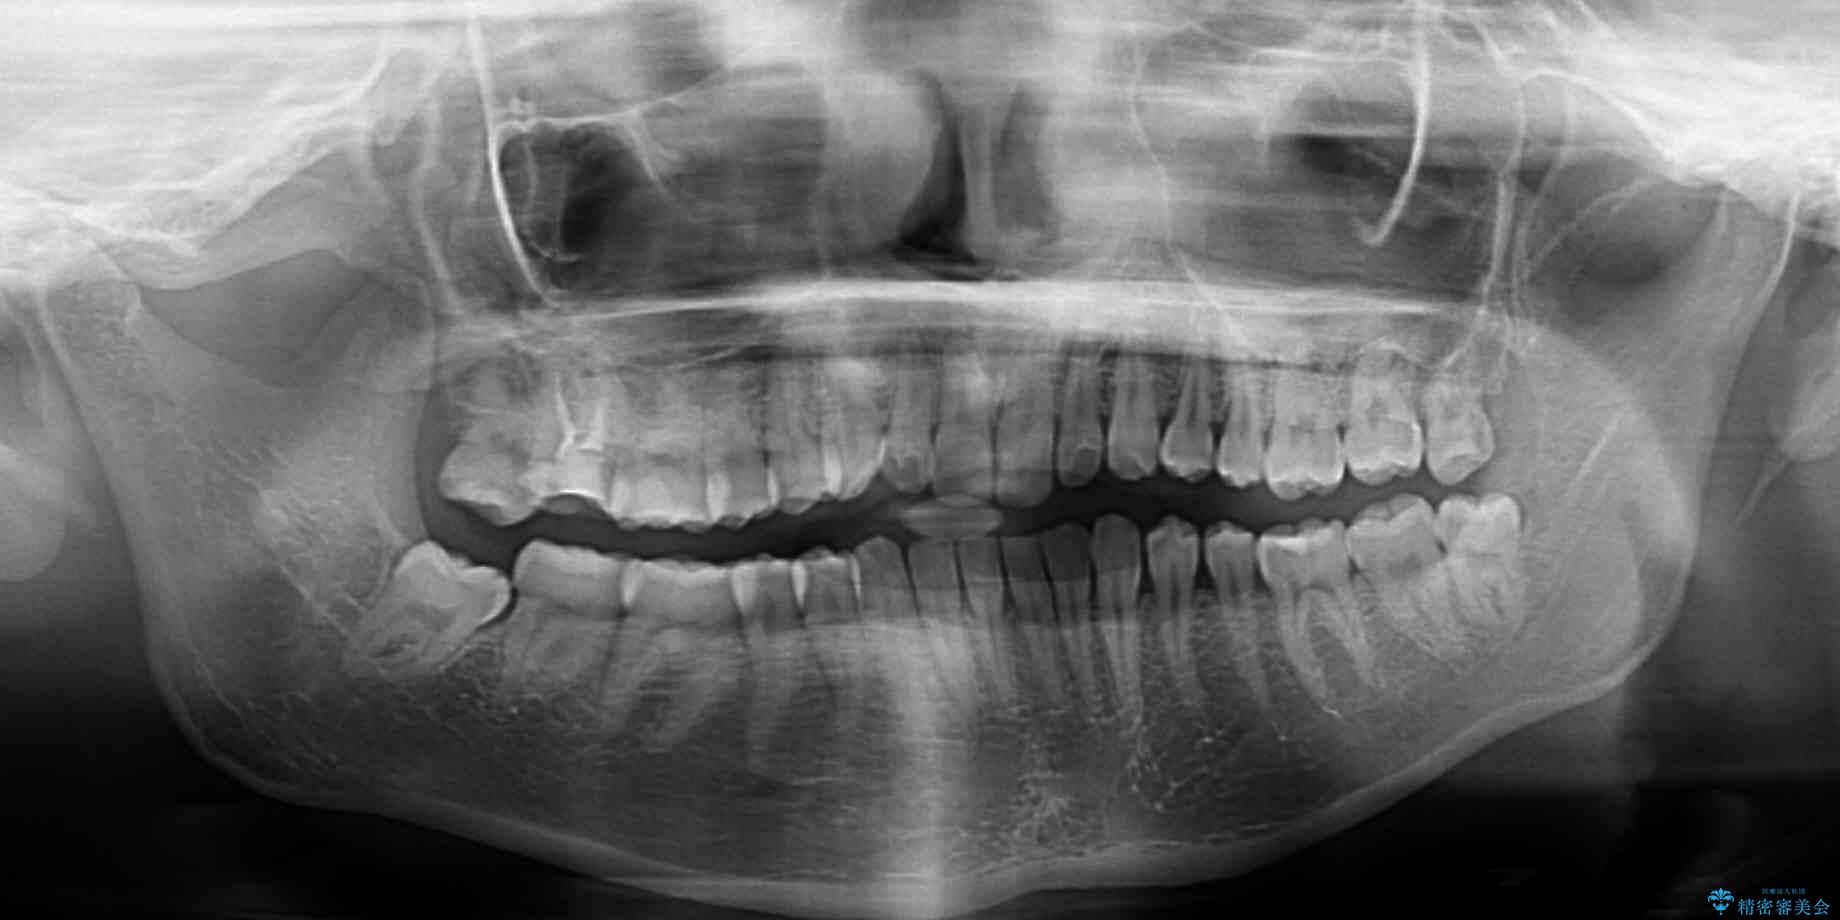

根管治療を行ったままの奥歯と、矯正治療の後戻りを気にして来院された患者様です。

根管治療された歯に症状はなく、オールセラミッククラウンにて補綴治療を行うこととしました。

治療前

• 治療途中の奥歯と矯正治療の後戻り インビザライン・ライトによる矯正治療 治療前画像